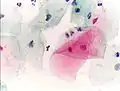

Micrograph of a Pap test showing trichomoniasis. Trichomonas organism seen in the upper right. Pap stain.

Infestation by Trichomonas vaginalis